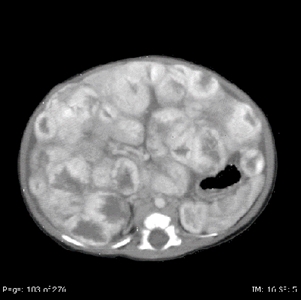

On MRI, vascular tumors of the liver are hyperintense on T2 imaging and hypointense on T1 imaging, with postcontrast imaging demonstrating early peripheral enhancement with eventual diffuse enhancement.[76] In practice, these tumors have been classified according to their clinical characteristics and radiological assessment.[76,154] In general, hepatic vascular tumors can be benign or malignant.